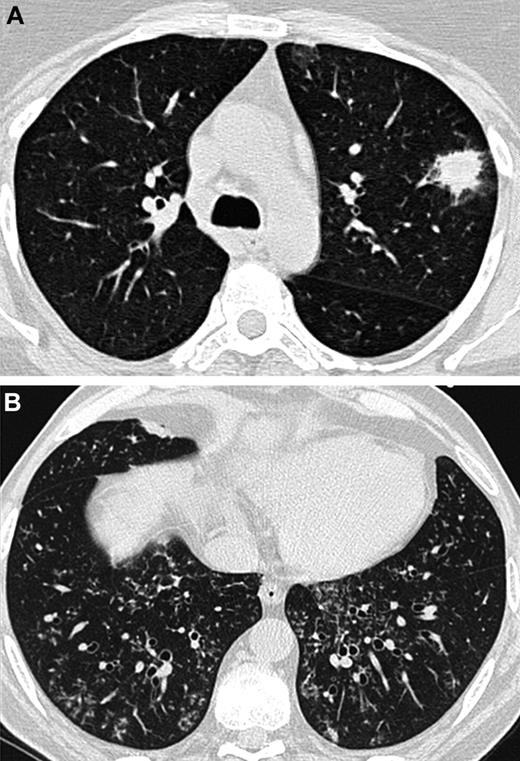

At baseline, lung HRCT scans were performed on each patient using multidetector CT scanners. A Data Review Committee reviewed and analyzed the lung CT scans (A.B., C.d.B., and K.C.). The following features were noted: nodules with or without halo sign or cavitation (in particular air crescent sign), alveolar consolidation with or without halo sign or cavitation, centrilobular micronodules and tree-in-bud opacities, ground glass opacities, septal thickening, and pleural effusion. Particular attention was paid to differentiate features that are known to be attributed to angioinvasive aspergillosis and those indicative of airway-invasive aspergillosis: in accordance with what was previously demonstrated in patho-radiologic correlations, the presence of a nodule with a halo sign without any airway-invasive features was defined as an angioinvasive disease (Figure 1A). In contrast, the presence of centrilobular micronodules and/or tree-in-bud without any nodule with a halo sign was defined as an airway-invasive disease (Figure 1B).7,9,11-13 As consolidations may occur with both aspergillosis-induced hemorrhagic infarctions (ie, angioinvasive disease) and Aspergillus bronchopneumonia (ie, airway-invasive disease), consolidations were not considered when differentiating between the 2 entities.10,12,13

Lung CT scans from 2 different patients. (A) Nodule with a halo sign revealing angioinvasive aspergillosis in an AL patient. (B) Centrilobular nodules and tree-in-bud opacities showing airway-invasive aspergillosis in a patient who underwent an allogeneic HSCT.